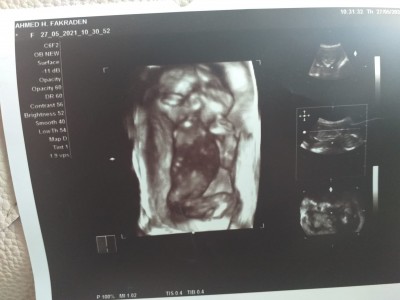

KIZLAR SIZCE CINSIYET NEDIR TECRÜBELİ ANNELER ??

17

Bu hafta ya kadar doktor bişey demedi mi

Kıza benzyor

Canım net deil dedi bugün gittim ayrıntılı 'yi bekle dedi

Birde bacakları kapalı sanki 4 boyutlu da öylemi benmi yanlış görüyorum

Bacak arasi boş bnce kiz

Bacakları kapalı degilmi nasıl anlıyorsunuz canım ben hiç anlamiyorum:))